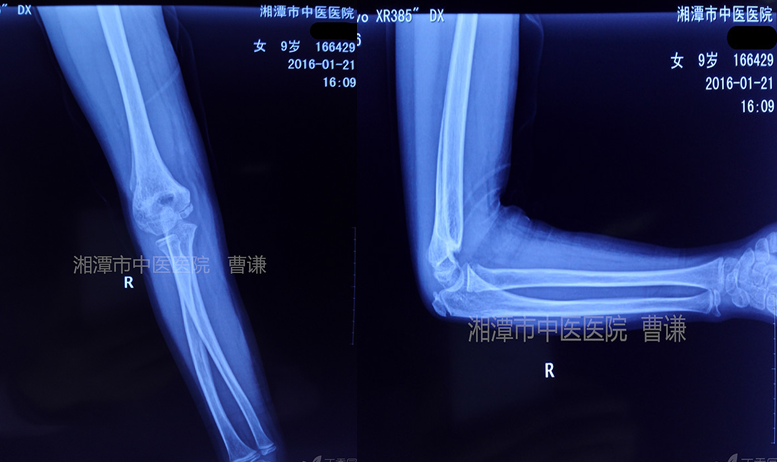

下面我們來看一例典型病例,患者:女,9歲,跌倒致右肘部畸形、腫痛、活動受限,就診于我院,拍片診斷為Gartland 型肱骨髁上骨折。入院行楊氏四步復(fù)位法手法整復(fù),小夾板外固定。入院拍片如下: